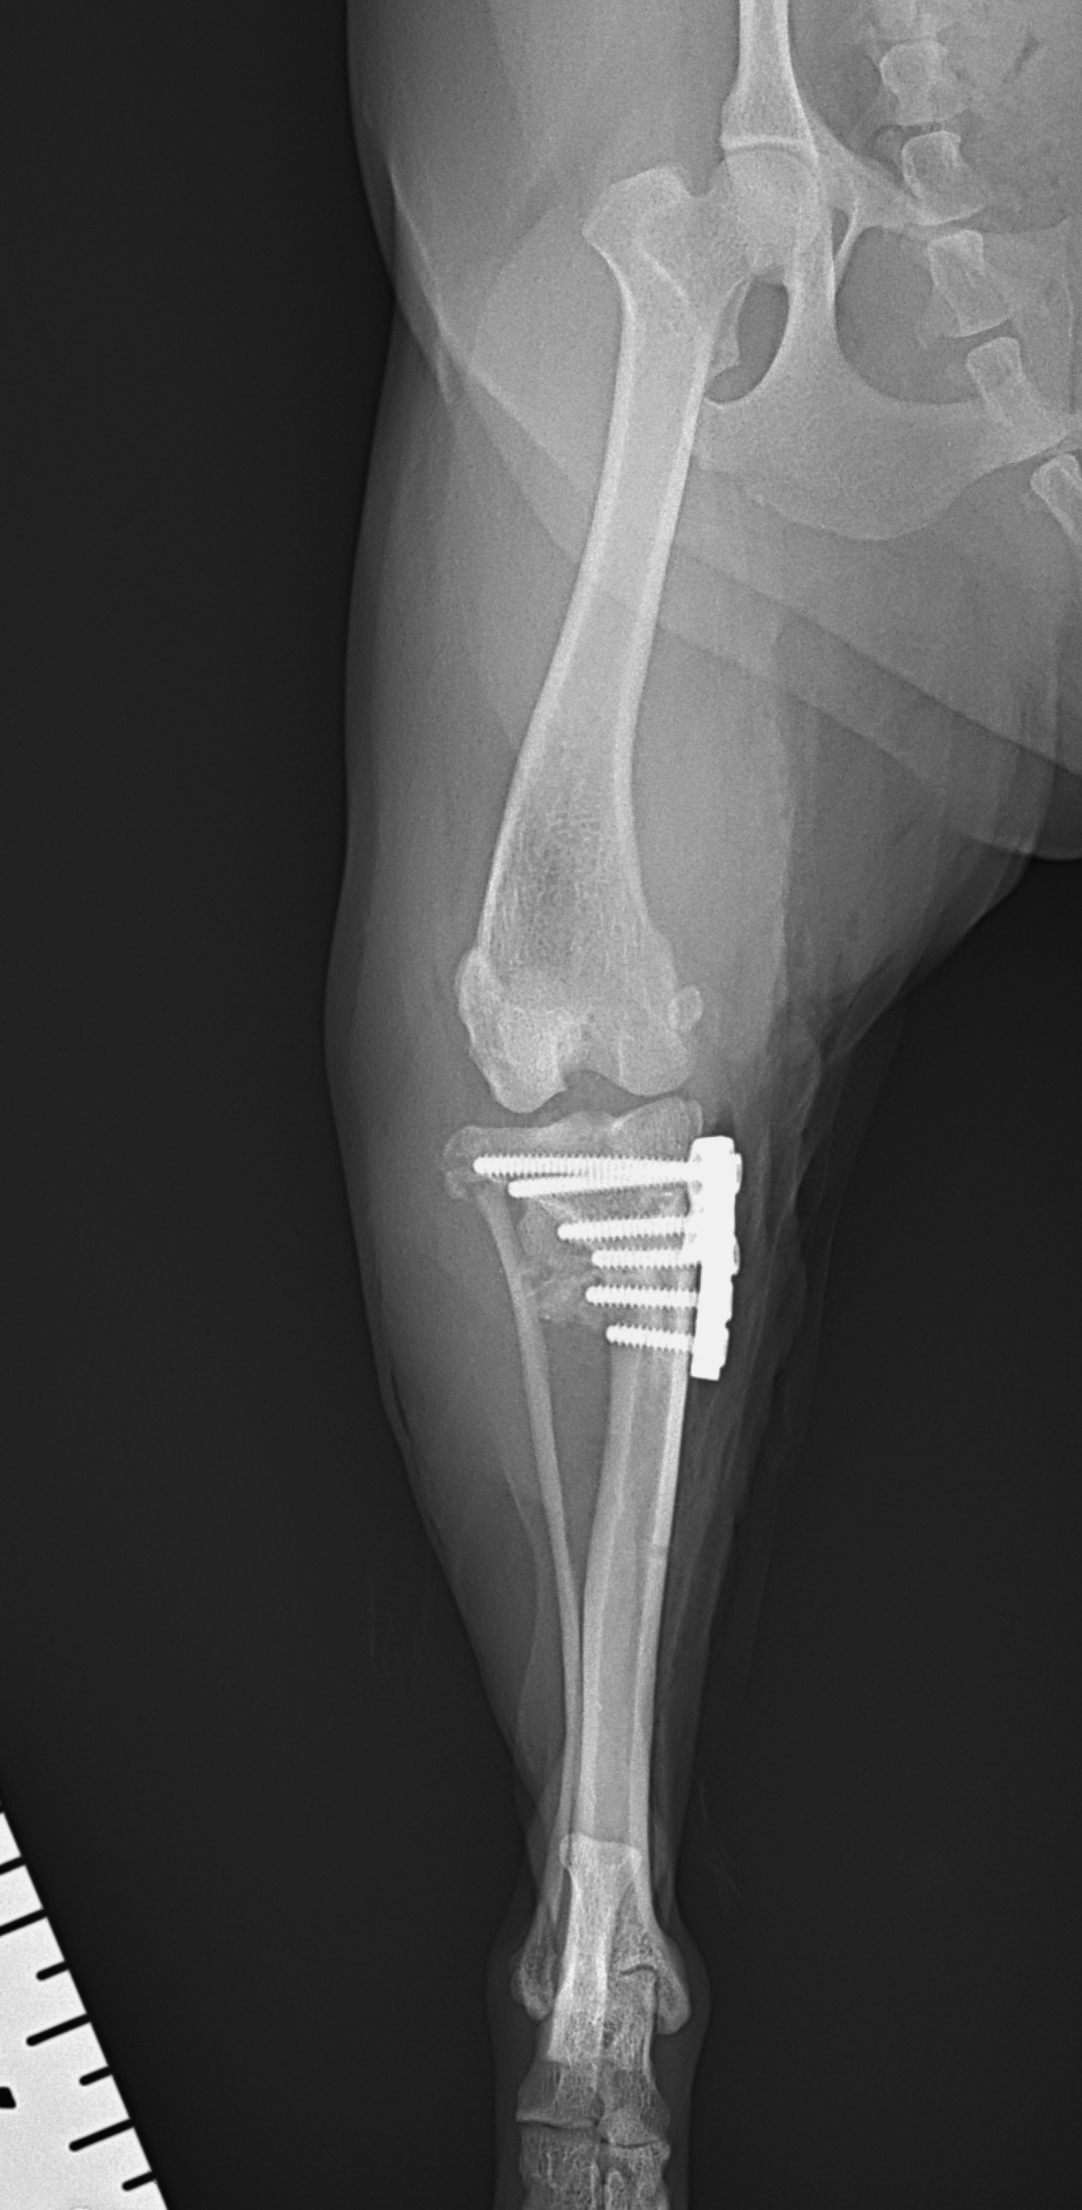

Toy Poodle×マルチーズのMix犬が前十字靭帯断裂により跛行が持続しているとのことでかかりつけ医より外科手術のために紹介来院されました。過去に膝蓋骨内方脱臼の手術を受けています。脛骨粗面移行術で使用されていたピンを除去したのち、CBLOで対応いたしました。しばらく安静が必要です。